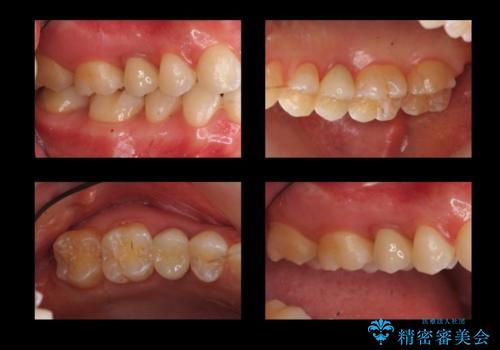

セラミックにする前後でマウスピース矯正治療を行なっています。(以下のリンク参照)

- 21万円(右上4:ジルコニアクラウン10万円、仮歯 1万円、歯周外科治療(APF) 10万円、矯正用仮歯 2万円費用は治療当時の料金となります

角化歯肉の幅がしっかり合ったため、歯肉をずらすAPF(アピカリ)でなく、切除療法を行いました。

骨外科の量は多かったですが、術直後見られた動揺も治っています。